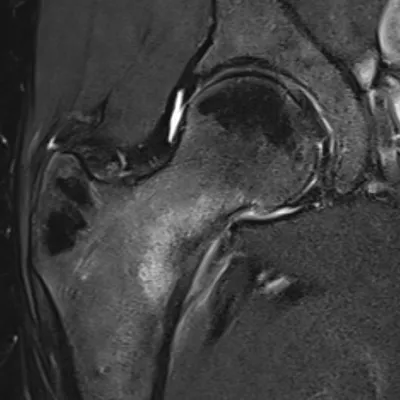

Osteochondral lesion of talus

MRIAnkleSagittal+2

5/1/2026